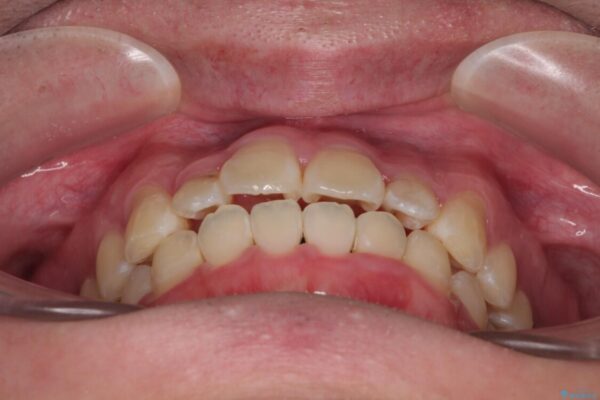

「歯並びがデコボコしていて、上下の中心がズレているのが気になる…」という悩みで来院された患者さまの症例をご紹介します。

初診時の状態

・上下ともに歯がきれいに並びきらず、がたつきが見られました。

・上下の前歯の中心(正中)がずれています。

・特に上顎の幅が狭いため、下顎の歯列も内側に入り込み、歯が並ぶスペースが不足していました。

治療前

• 1年でここまで変わる!歯列のがたつきと正中のズレを改善した矯正治療(メタルブラケット×MARPE) 治療前画像